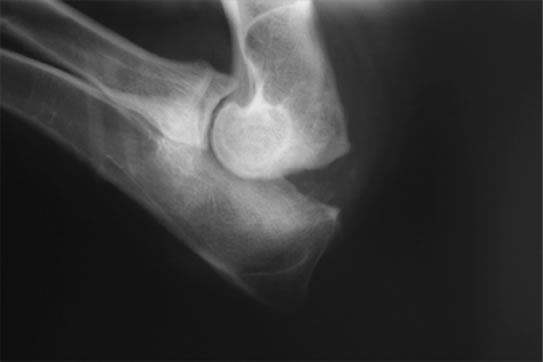

肘関節形成不全症 / UAP(肘突起分離症)

肘関節形成不全症 / UAP(肘突起分離症)とは

肘突起の 肘頭への癒合障害により痛みが生じます。

診断

レントゲン検査、関節鏡検査

治療

分離した肘突起の肘頭への固定、分離した肘突起の切除